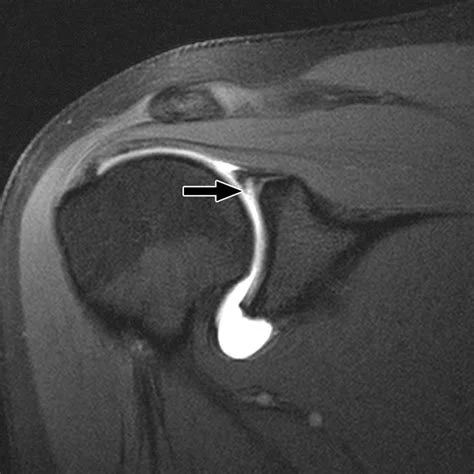

An Arthrogram is a type of CT or MRI, where a contrast agent is injected directly into a joint before the area is scanned (shoulder, knee, wrist, ankle, etc) so that a more comprehensive image and accurate diagnosis of the soft tissue injury can be determined. This dye outlines cartilage, ligaments, labrum and joint spaces.

Your GP or Specialist may request this in addition to a general CT or MRI to identify ligament tears (labral tears or rotator cuff tears), meniscal injuries or cartilage defects.

MRI scan of a knee showing a meniscus tear.

Example of Arthogram